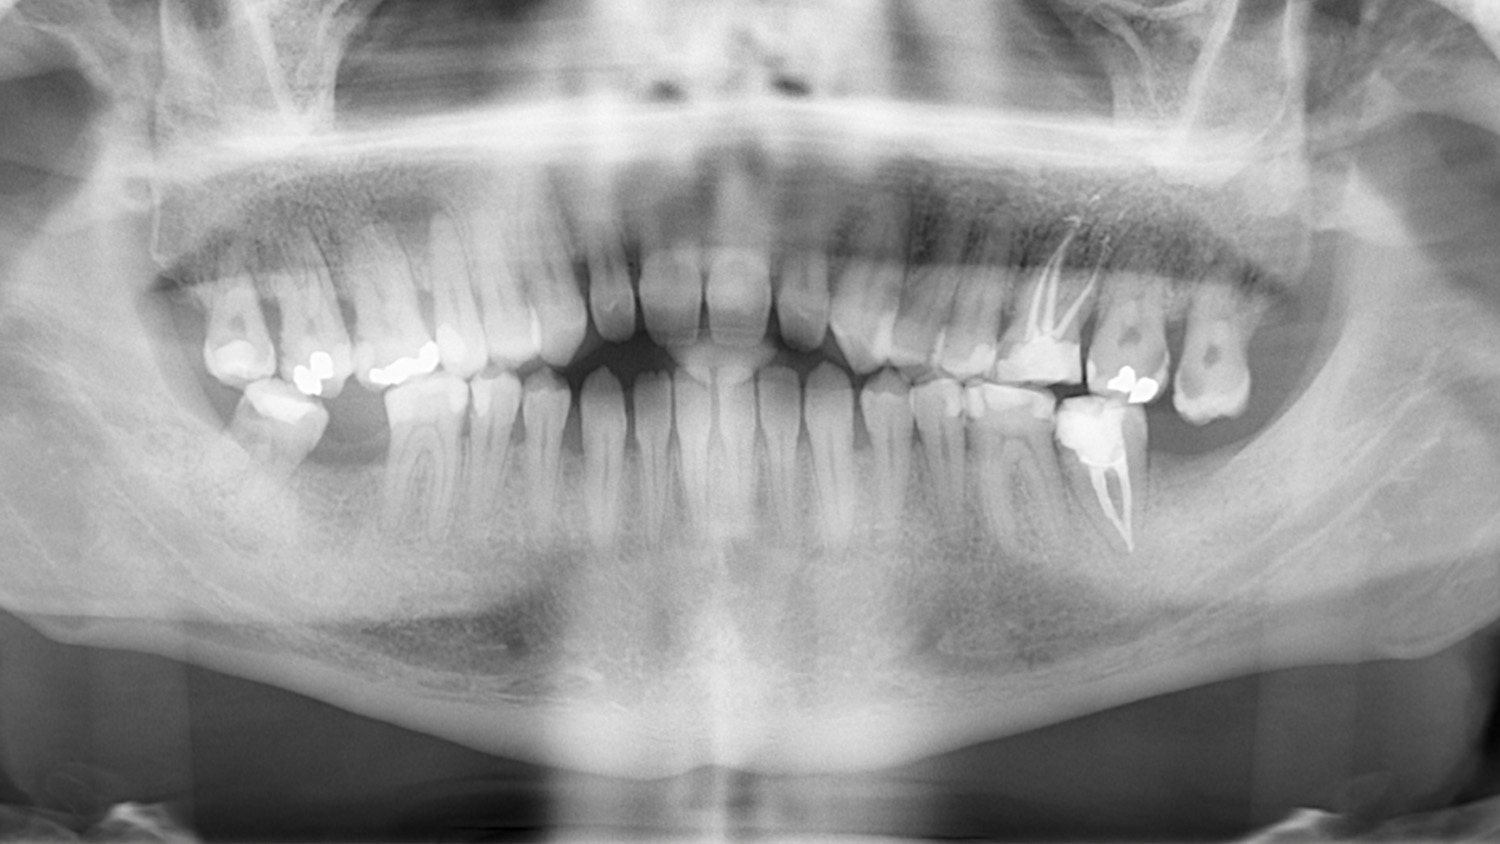

A 27-year-old male patient presented to the orthodontic practice after being referred by his general dentist. His primary concern was improving masticatory function. The patient had no notable medical history, nor had he received prior orthodontic treatment.

Intraoral examination showed an Angle Class III relationship on both sides, along with an anterior open bite. Additionally, a narrow maxilla with a bilateral posterior crossbite was observed.

The patient was informed of various treatment options, including combined orthognathic surgery and orthodontic appliances. However, he opted against surgery. Consequently, a compensatory orthodontic treatment plan using MARPE (Mini-Implant Assisted Rapid Palatal Expander) and Spark Aligners was chosen, after the extraction of the existing third molars and treatment of the cavities.

Ultimately, we successfully corrected the crossbite, open bite, and Class III canine relationship. The patient rehabilitated tooth #26 with an on lay and tooth #47 with an implant, resulting in a stable occlusion. Post-treatment retention involved a fixed retainer in the lower arch and removable retainers for both upper and lower arches to maintain the treatment results.